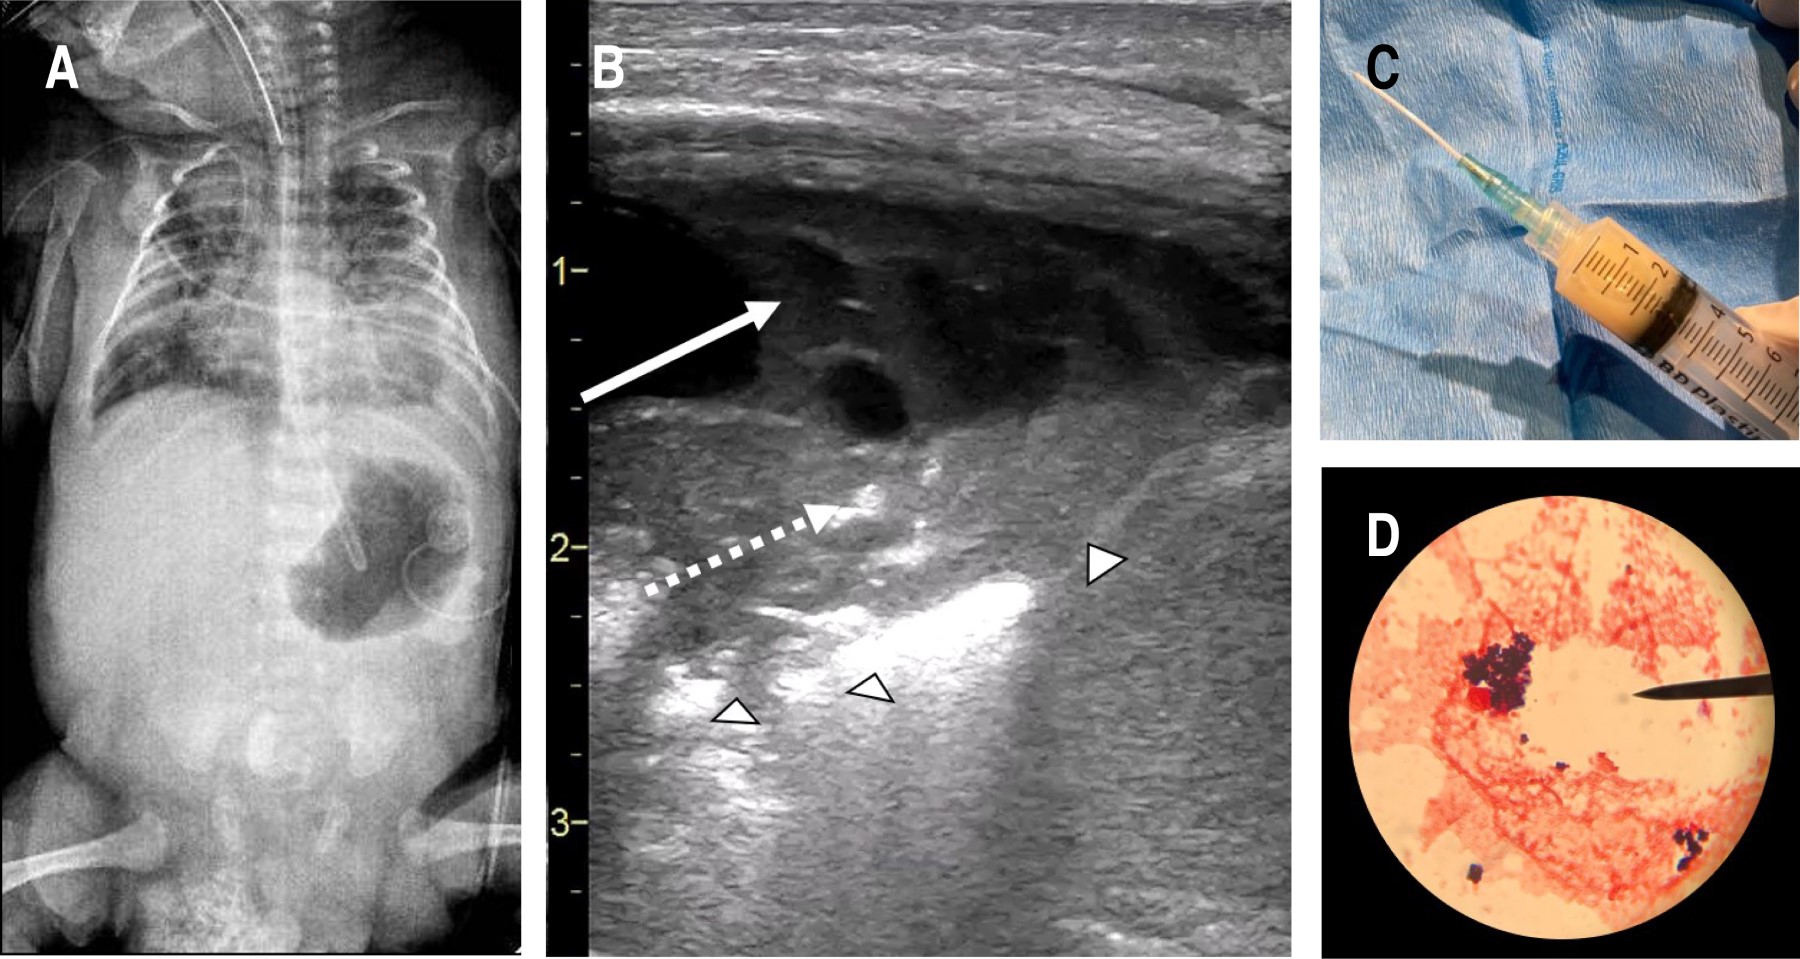

La radiografía de tórax mostró infiltrados en campos pulmonares y un probable derrame pleural izquierdo (Figura 1A). Mientras que el ultrasonido cardiaco reveló un CAP restrictivo, no significativo. En la revisión pulmonar con ultrasonido se evidenció derrame pleural complejo (Figura 1B, flecha), identificando el "signo de la disrupción" (Figura 1B, cabezas de flecha) y la consolidación con broncograma "fluido" (Figura 1B, flecha punteada). Posteriormente, también guiado por ultrasonido, se extrajo líquido purulento (Figura 1C) con características de exudado, en el cual se identificaron cocos Gram positivos (Figura 1D). Se obtuvo aislamiento de Staphylococcus aureus en líquido pleural y hemocultivos, por lo que se brindó tratamiento con cefalotina por 14 días, resolviendo el cuadro clínico.

Como en reportes previos, este caso demuestra la utilidad del ultrasonido para la identificación de focos neumónicos, mediante la visualización del signo de la disrupción, broncograma y derrame pleural,2 además ayudó a guiar la extracción de líquido pleural. Muy probablemente, estas acciones permitieron evitar complicaciones e inclusive la muerte.3,4